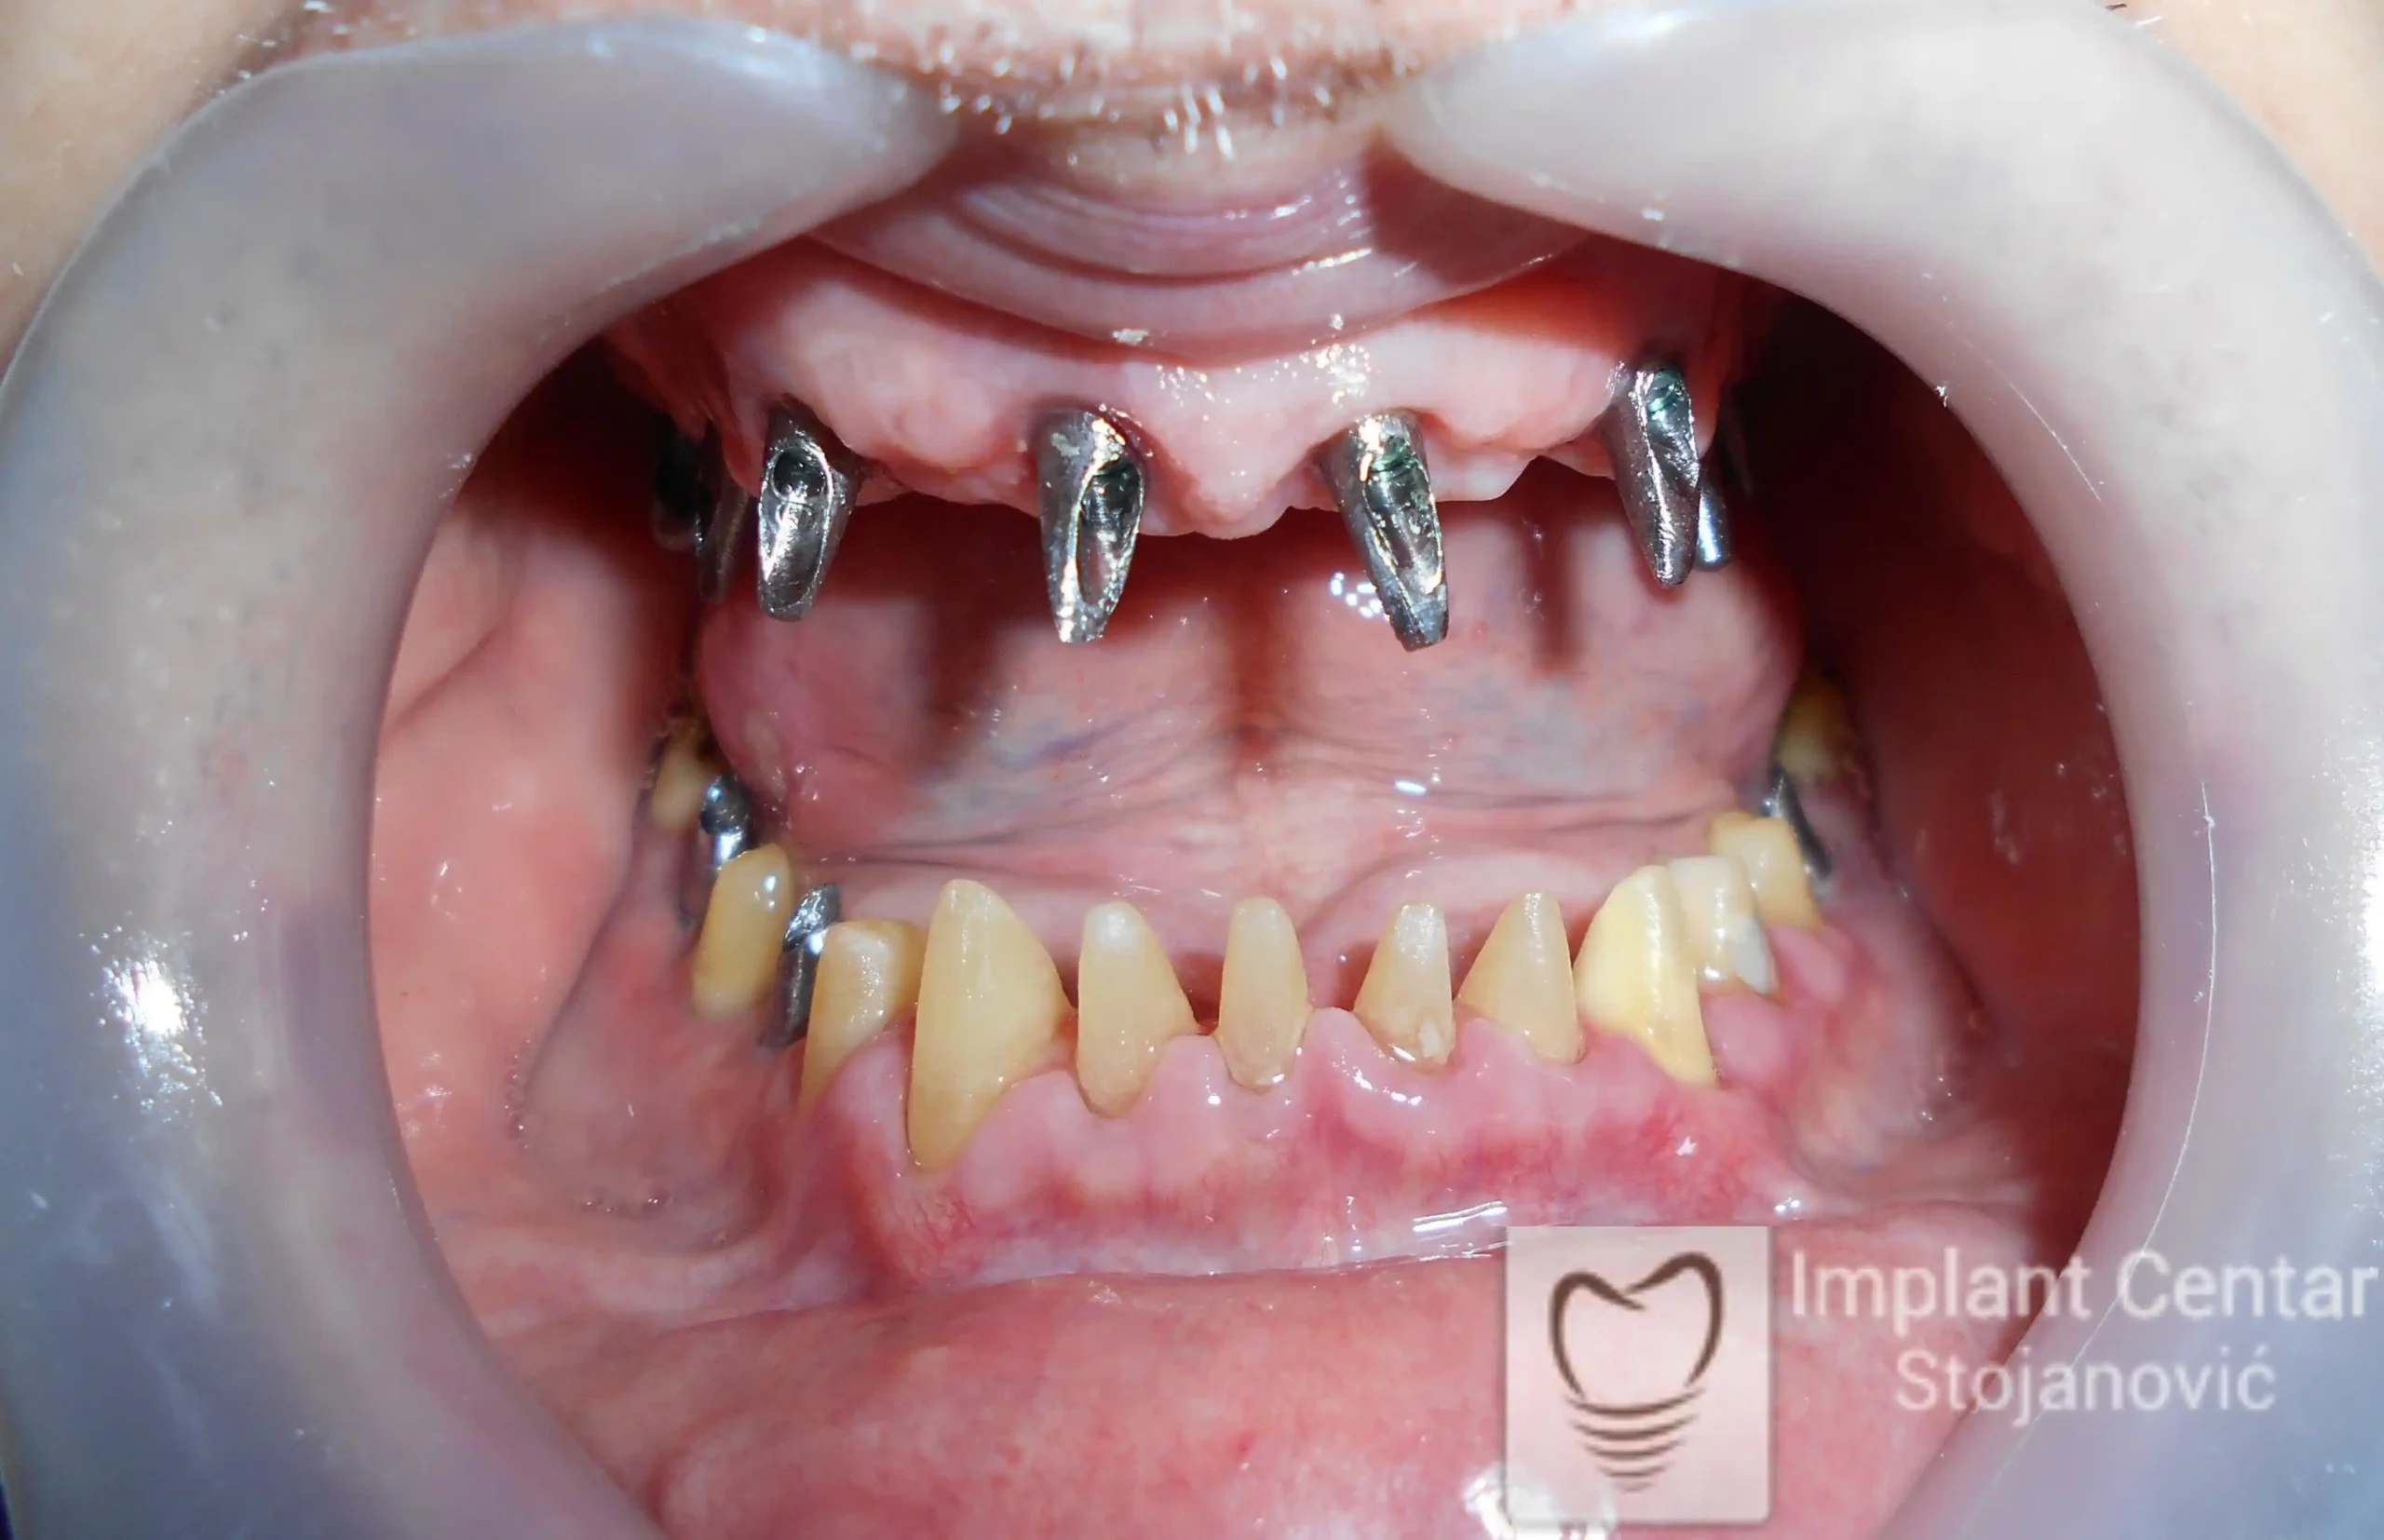

Na slici 1. slici 2. vidi se početno stanje — pacijent je imao prirodne zube, ali samo izradom novih mostova nije bilo moguće postići normalan odnos gornjih i donjih zuba (eugnatan zagrižaj).

Zbog toga je plan terapije uključivao vađenje svih preostalih zuba i ugradnju implantata u gornjoj i donjoj vilici. U gornjoj vilici postavljena su i dva tuberopterigoidna implantata, kao zamena za sinus lift proceduru, što se može videti na ortopan snimku nurađenom odmah nakon ugradnje (slika 3).